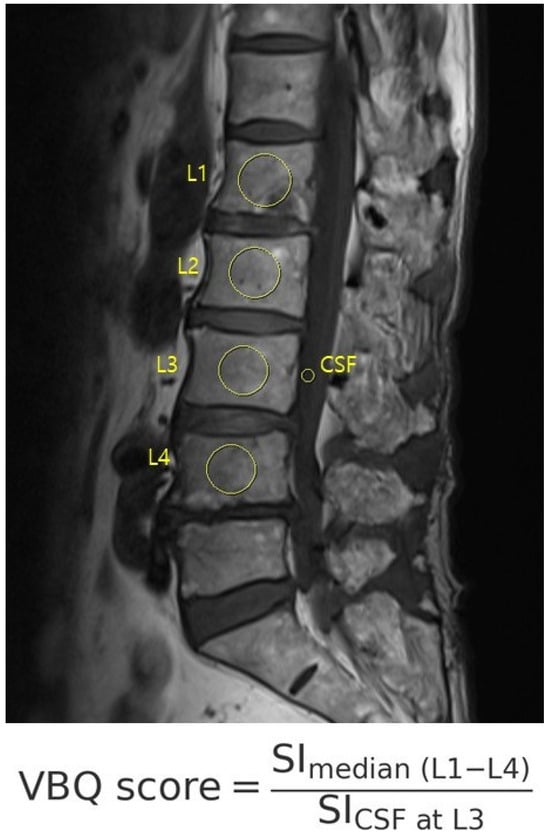

The VBQ score was calculated using non-contrast, T1-weighted MRI acquired with a 1.5 T scanner (Figure 2). ROIs were manually placed (1) within the medullary portion of L1 to L4 vertebral bodies and (2) within the cerebrospinal fluid at the L3 level. The VBQ score was defined as the ratio of the median signal intensity of the vertebral bodies to that of the cerebrospinal fluid (CSF). VBQ score = SI_ median(L1–L4)/SI_CSF at L3. Measurements were independently performed by two trained researchers who were blinded to the quantitative computed tomography (QCT) results. One investigator repeated the measurements for intra-rater reliability. The final VBQ score was the mean of four measurements [12,13,14]. MRI was performed using a 1.5-T scanner (MAGNETOM Vida, Siemens Healthineers, Erlangen, Germany).

Figure 2. The VBQ score was calculated on T1-weighted MRI as the ratio of the vertebral body to CSF signal intensity, using manually placed ROIs from L1 to L4 and CSF at L3.